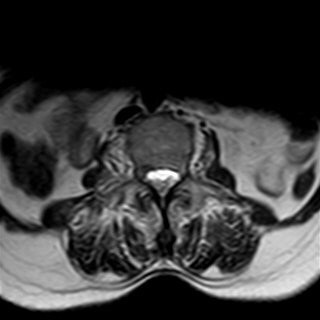

Needed help for this currently admitted 60 years old woman with gradual paralysis and severe back pain for the last few weeks. On examination there was slight gibbus and absent lower limb reflexes and MRI shows a lesion at L3 as well as T3.

Radiological images: